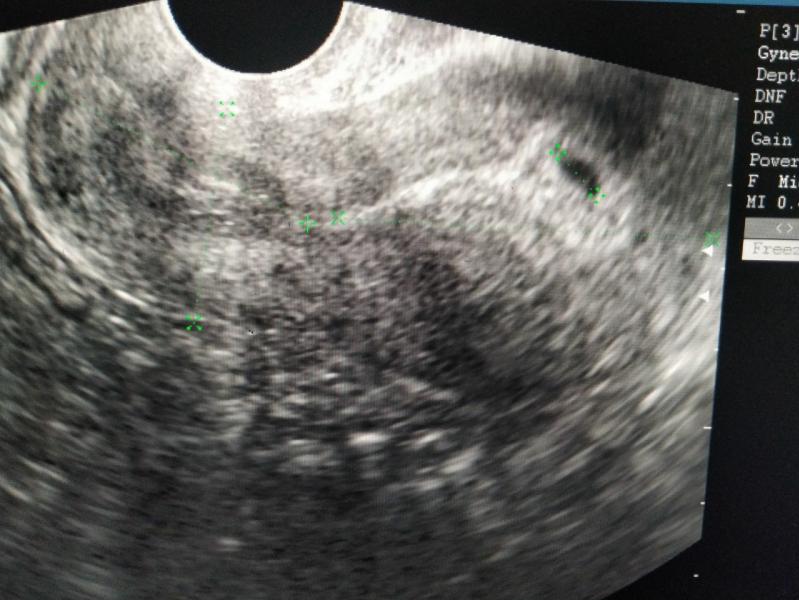

🚑 Сохранение - да (14 неделя)